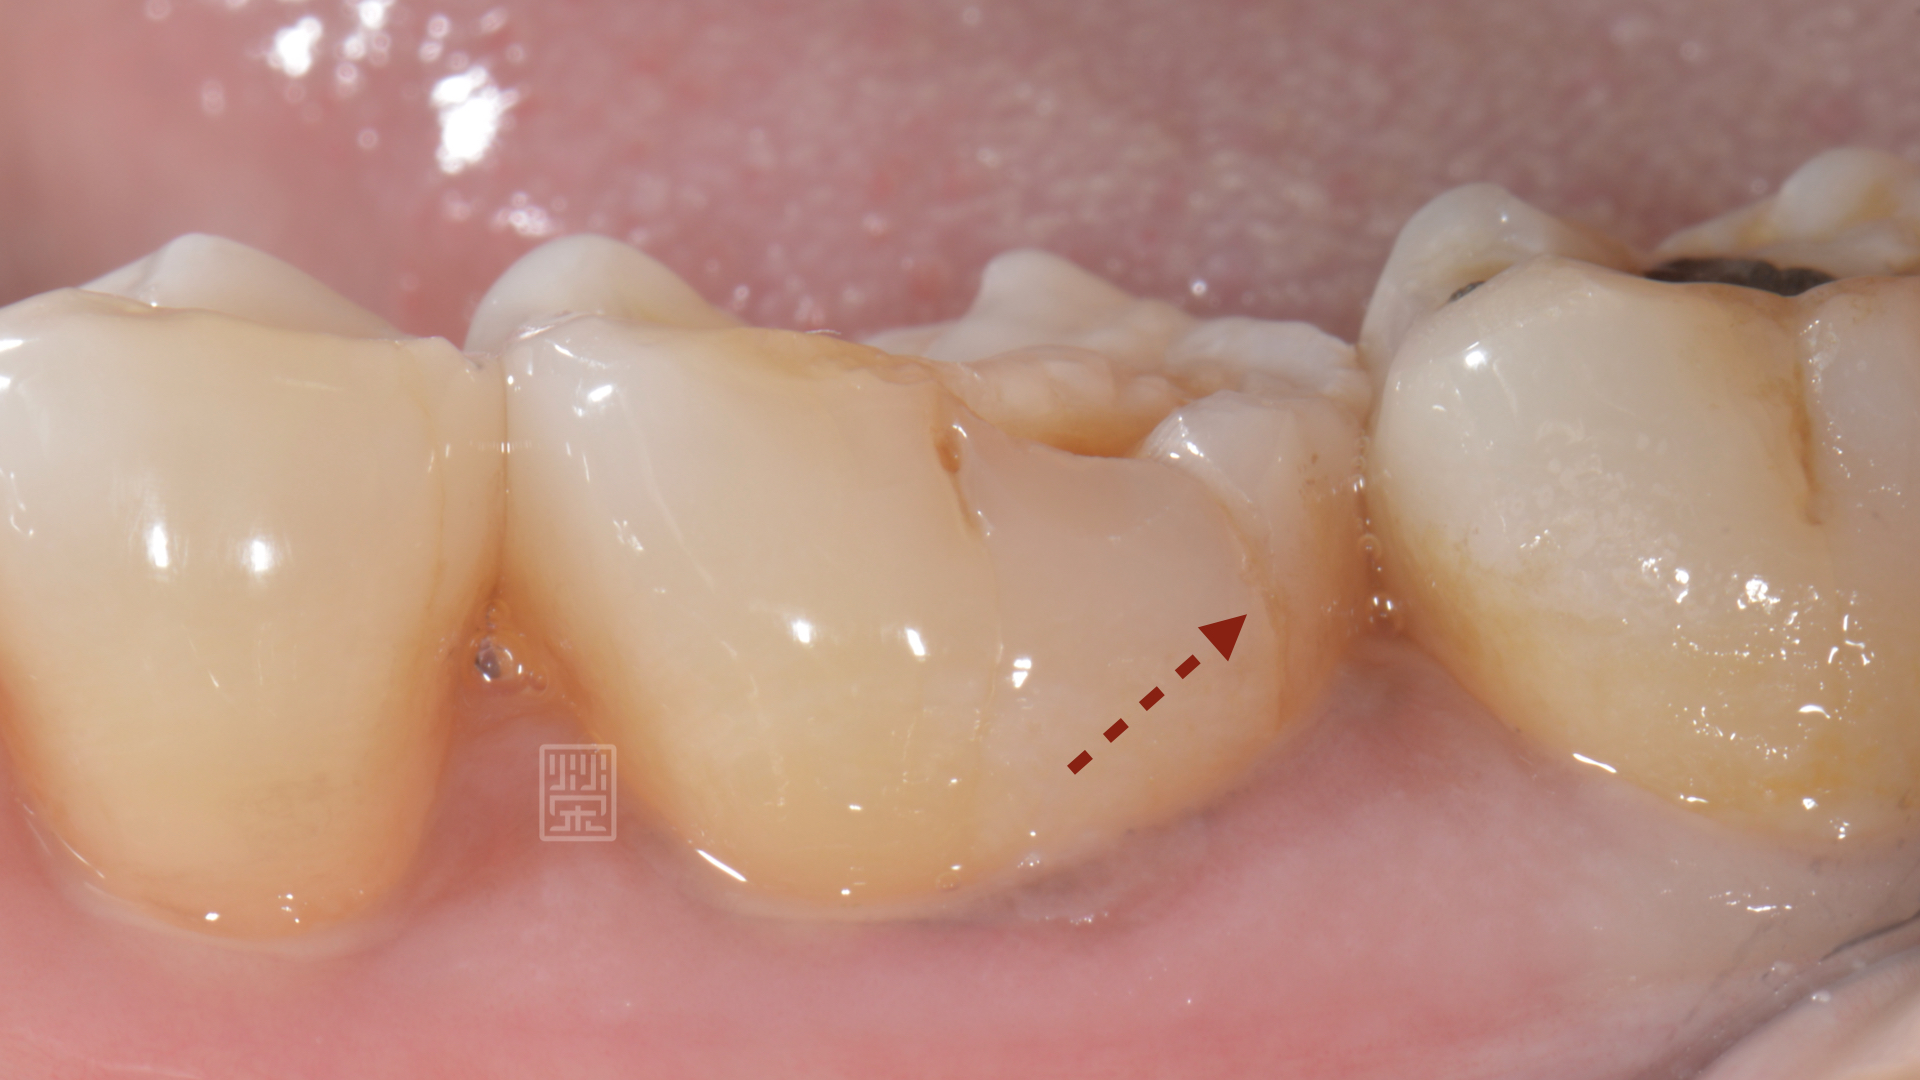

牙齒修磨